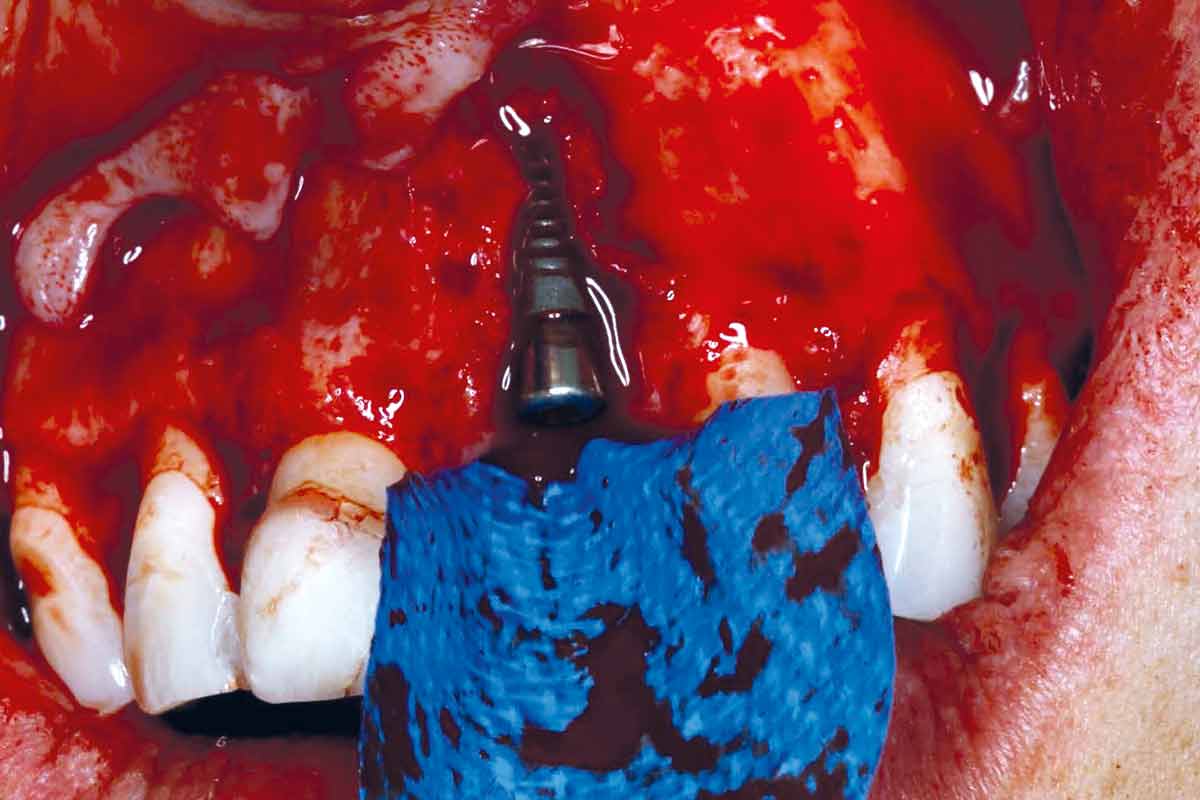

Implant placement and bone augmentation in the aesthetic zone using maxgraft® and permamem® - Dr. A. Puišys

Implant placed in the deficient site. permamem® in place for covering.

Initial situation – Treatment plan: Replace the adhesive upper left central incisor bridge with a dental implant